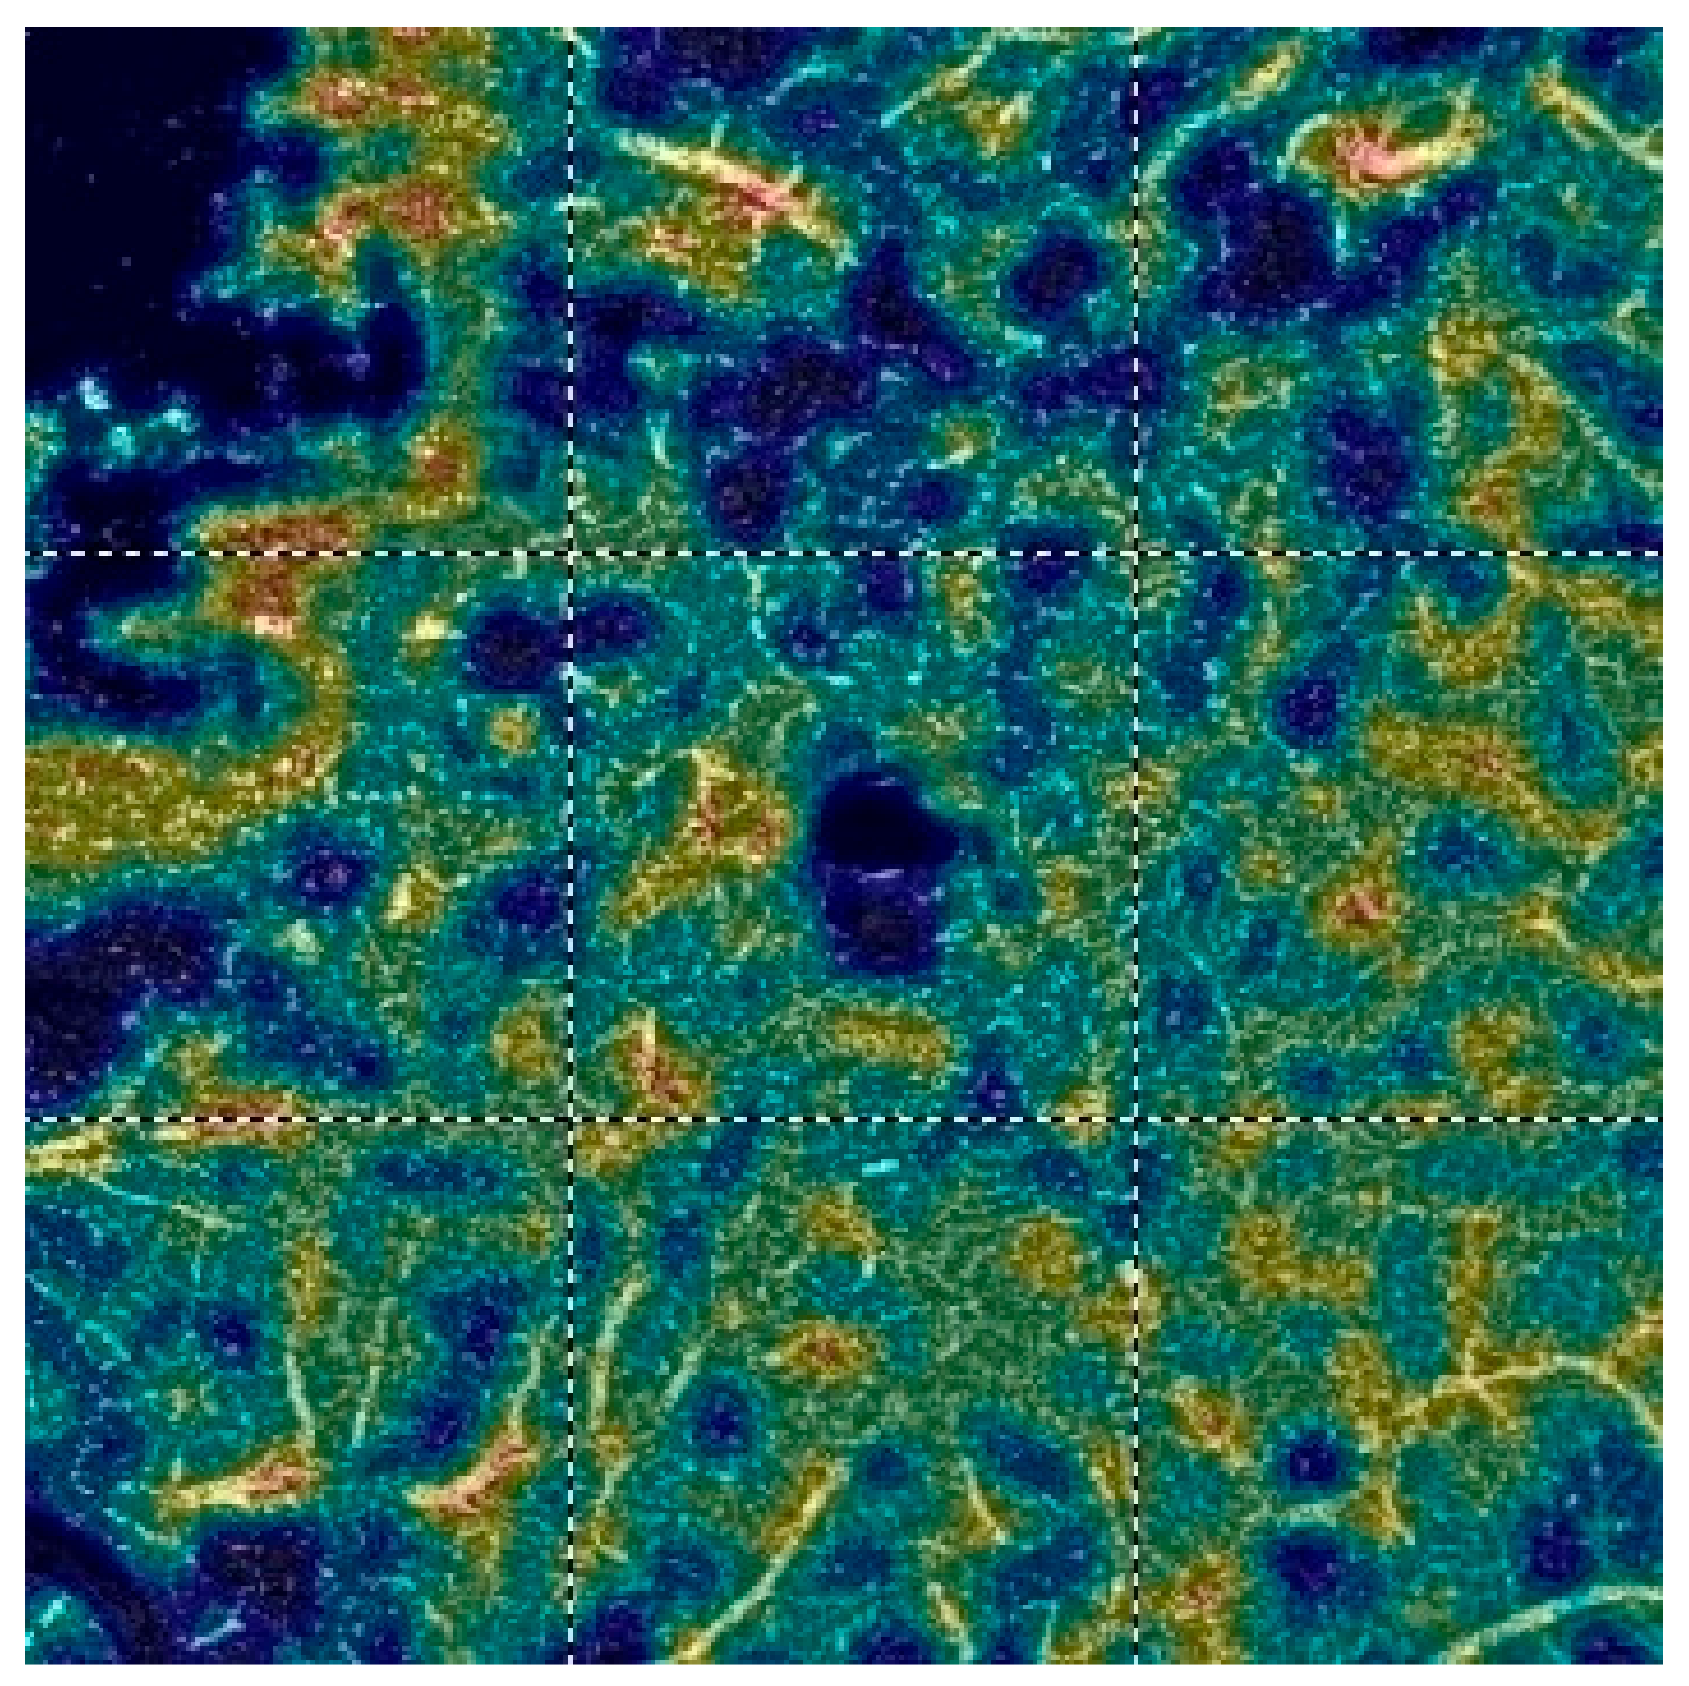

7. Examples of OCT-A Scans before and after Treatment